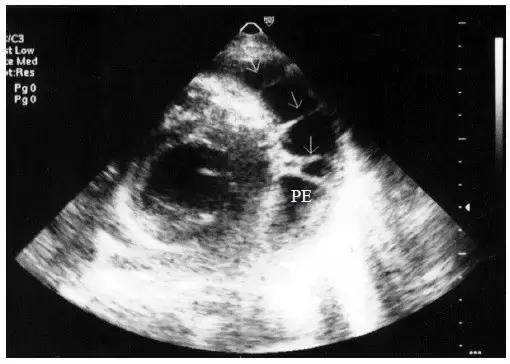

【少量心包积液】

液体仅潴留在左心室后壁和侧壁心包腔内,内径<10mm(图1)。

图1 少量心包积液的二维超声心动图表现

左心室后壁心包腔内少量液性暗区,内径< 10mm